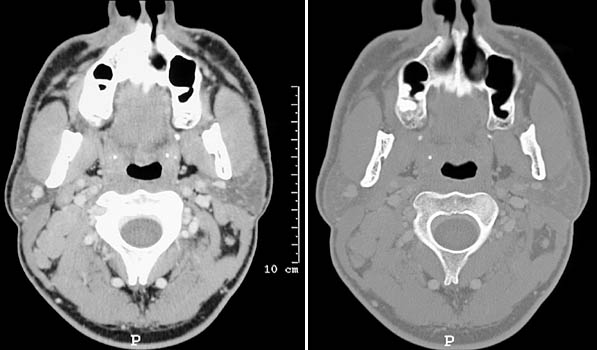

| There is massive lymphadenopathy involving the spinal accessory chain of lymph nodes posterior to the sternocleidomastoid muscle and the parotid gland at the level of the angle of the mandible in this head and neck CT scan in bone and soft tissue windows. A biopsy revealed Hodgkin's disease. |